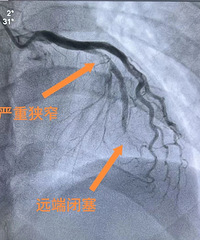

台州33岁小伙睡梦中遭遇心梗!这家医院又连救3名急性心梗患者